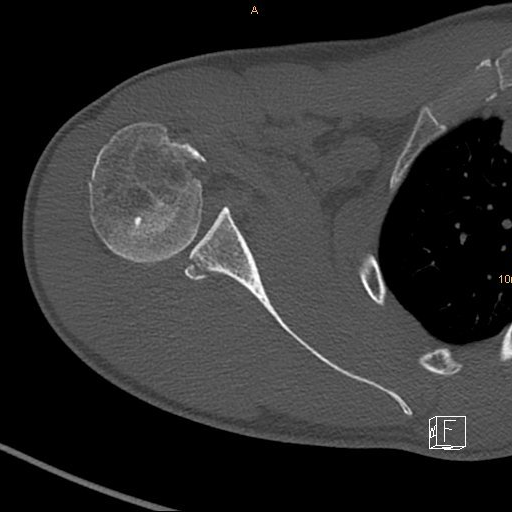

TP1 and TP2 together form the cluster Facto rs. In TP2 (Protein Production), these proteins are produced recombinantly. The mechanism of action of the biologically active proteins for formation of tendon-bone-junctions in the adult system is elucidated within subproject (TP) 1 (Biological Mechanisms). The work tasks within the research unit are divided between four clusters: Facto rs, Manufacture/Carrier, Release, In vivo -Use. For fixation of the implant within the tissue stitching will be performed on the tendon side, and bone anchors will be used on the bone side./em> The nanoparticles represent different binding and release systems. The gradients existing in vivo are here mimicked by gradients in the mechanical properties as well as gradients in spatial and temporal release orf bioactive proteins. die Knochenoberfläche, sind aber nicht lasttragend. Die Fäden dienen der Anpressung des Implantats an den Sehnenstumpf bzw. Die Ermittlung der optimalen Implantationstechnik (Einsatz des Implantats in Augmentation oder Interposition) ist Teil des Arbeitsprogramms von TP8 hier ist die Augmentation dargestellt. Rechts vergrößert: Mit dem Implantat versorgter Defekt. Right enlarged: Defect with implant positioned in augmentation technique.hematische Darstellung des Implantats an der Rotatorenmanschette (die rechte Schulter ist in der Vorderansicht dargestellt). Schematic drawing of the implant at the rotator cuff (right shoulder, front view). In the second funding period (started in January 2019) seven subprojects are included. In the first funding period, eight subprojects contributed to the research unit. By this conception, it will be safe for the patient as well as efficient and as simple as possible in its production and use, thereby promoting its translation into a commercial product. Consequently, it is bioinspired and biomimetic but cell-free and supposed to mediate bioactivity. figure) is supposed to restore a tendon-bone junction, both in vitro and in vivo. By virtue of being equipped with different gradients, the implant (cf. In the human setting, the necessary dimensions are about 25 mm in length (mediolateral) and 30 to 40 mm in width (anteroposterior). The implant is supposed to work for the rotator cuff which is a complex of several muscles and their respective tendon-bone-junctions at the shoulder (cf.

The tissue formation after use of the implant is verified in vivo in small and large (sheep) animal models. The fixation of the implant on the bone side is achieved via commerically available bone anchors. For maintenance of long-term release, BMP2-aggregates and amyloid variants of Smad8 L+MH2 will be produced. In order to achieve spatially and temporally controlled release of these three proteins they are applied via nanoparticulate release systems in a controlled manner. The latter is a modified transcription factor that induces the formation of tendon cells and tendon tissue from adult stem cells. The mats are modified on the fibre surfaces and are equipped with varying amounts of nanoparticles: Polymeric nanoparticles will serve as release systems for biologically active proteins.Īpart from Bone Morphogenetic Protein (BMP)-2 (for bone region) and Transforming Growth Factor (TGF)-β (for cartilage region), Smad8 Linkerregion + Mad Homology Region 2 (Smad8 L+MH2) is used as a novel factor. Moreover, the mechanical properties of the fibre mats will mimick the in vivo-situation. the use of sacrificial fibres which will dissolve under physiological conditions) in order to provide a porosity and permeability that will allow survival and biological function of immigrating cells as well as exchange of nutrients and waste products. The fibre mats will be subjected to appropriate treatments (e. These mats will have parallel fibre alignment (on the tendon side) and non-oriented fibre alignment (bone side) within the same mat. As basic material electrospun fibre mats from biodegradable polymers (mainly based on polycaprolactone) will be used. Aim of the research unit is to demonstrate, in principle, the feasibility and exemplary generation of a graded implant for future use at the tendon-bone junction of the rotator cuff.